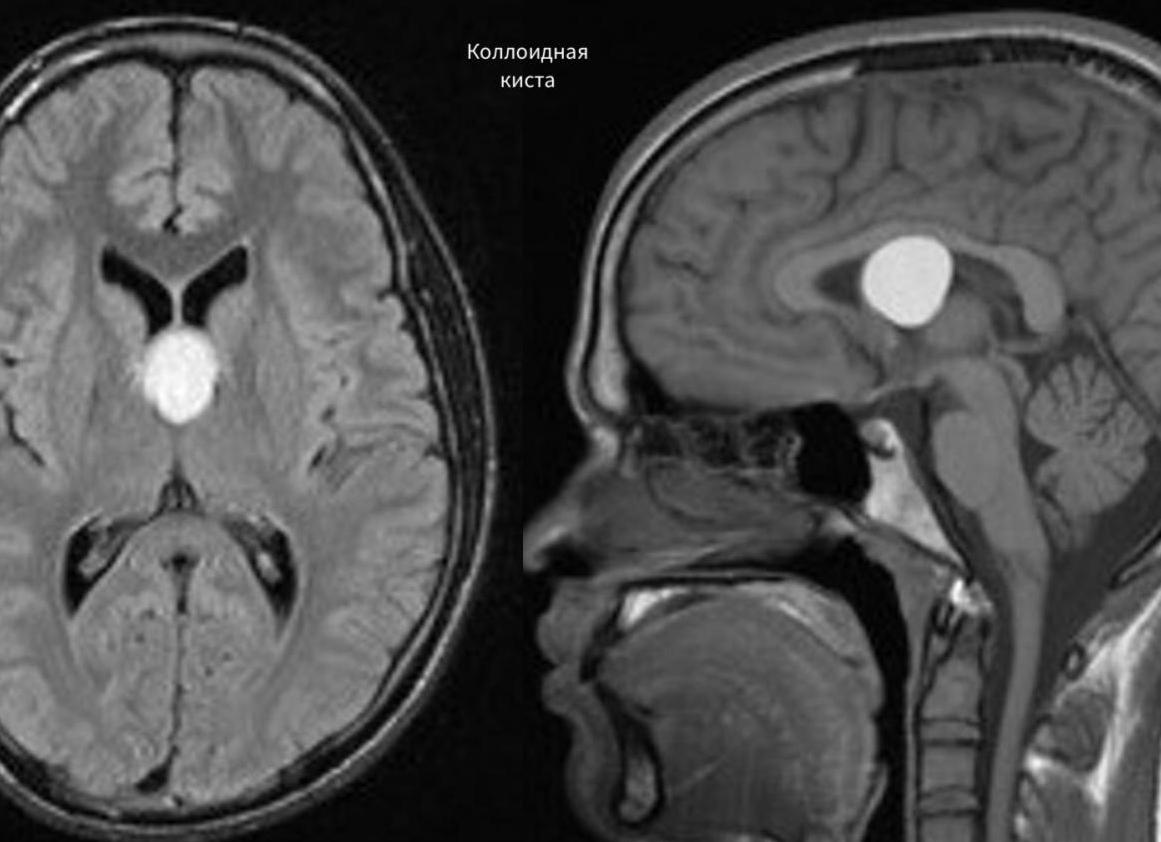

Врожденная киста головного мозга формируется непосредственно во время внутриутробного развития плода. Она разделяется на коллоидную и дермоидную формы. Коллоидная форма подразумевает под собой образование полости, внутри которой содержится желатинообразная субстанция. Такой дефект приводит к блокировке оттока жидкости из головного мозга с последующим нарастанием признаков гидроцефалии. Дермоидная форма устанавливается в том случае, если в сформировавшейся полости содержаться частицы эктодермы, волосяные фолликулы, а также сальные железы.

2. Коллоидальная киста. Это образование появляется как результат эмбриогенеза. Такая киста может не тревожить человека на протяжении всей жизни, однако иногда она блокирует ток ликвора. Поэтому возможно возникновение гидроцефалии, мозговых грыж, а иногда это даже приводит к внезапной смерти.

Коллоидальная

Участков сосредоточения этого нароста остается третий желудочек головного мозга. Коллоидальная киста головного мозга представлена в виде полости, которая заполнена густой жидкостью желеобразной консистенции. Такой тип кисты носит унаследованный характер.

5. Киста коллоидная. Представляет собой доброкачественную опухоль, содержащую внутри себя коллоидную (желатинообразную) жидкость. Такая патология очень медленно растет, однако последствиями отсутствия лечения становятся атрофические изменения головного мозга.